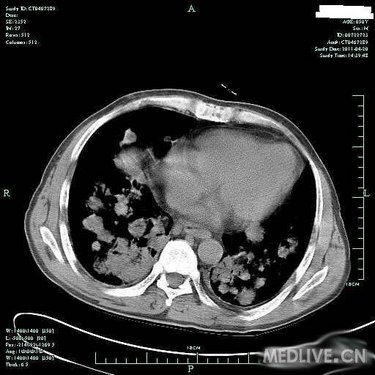

病史特点:患者于3月余前受凉后出现发热,体温为39.0摄氏度左右,伴咳嗽,为阵发性咳嗽,有咳痰,色白,有咽痛,无鼻塞及流涕,至当地诊所输液(具体不详)治疗后,效果不明显。于80天前入住当地医院,住院期间查胸部CT提示:双肺弥漫性结节影,纤支镜:双叶段粘膜轻度充血、水肿,痰找脱落细胞阴性,行左下肺经皮肺穿刺针吸细胞学未见异形细胞,曾予哌拉西林/他唑巴坦针、利福平、氟康唑针等治疗后,仍有反复发热,体温高达39.0摄氏度左右,发热时有气促感,无胸痛、头痛及心悸感。于2月余前至我院住院,CRP41.80mg/L,肺CT增强:两肺多发病灶,肿瘤不能排除,建议穿刺活检;气管镜检查:两侧支气管均通畅,未见新生物,气管镜刷片、肺泡灌洗液均未见肿瘤细胞;进一步行肺穿,肺穿刺涂片找到坏死组织,涂片未见肿瘤细胞,穿刺病理:(右)肺组织慢性炎伴坏死及淋巴组织增生;骨髓活检:造血细胞增生活跃伴散在T细胞浸润。予以出院带药HRE诊断性抗结核+SMZco治疗,患者用药不规则,仍有反复发热,最高达40摄氏度,伴畏寒,予退热药处理后热退,伴少量咳嗽及呕吐,无明显咳痰,复查肺部CT病灶对比前片增多、增大,为进一步诊治收住入院。

T 37.2℃,R 20次/分,P 82次/分,BP 114/79mmHg,神清,精神偏软,浅表淋巴结未及肿大,双肺呼吸音粗,未及明显干湿啰音,心律齐,瓣膜区未闻及病理性杂音,腹平软,无压痛及反跳痛,肝脾肋下未及,双下肢无浮肿,右上肢肌力IV级,握力差。

血常规(五分类)(病房):白细胞计数3.8×10E9/L,中性粒细胞(%) 84.8%,淋巴细胞(%) 4.7%,血红蛋白106g/L,血小板计数279×10E9/L。

血生化:总蛋白50.3g/L,白蛋白27.4g/L,球蛋白22.9g/L,白球蛋白比例1.2。 ANCA,MPO,PR3等检查未见明显异常。 癌胚抗原7.8ng/mL,神经元特异性烯醇化酶44.0。